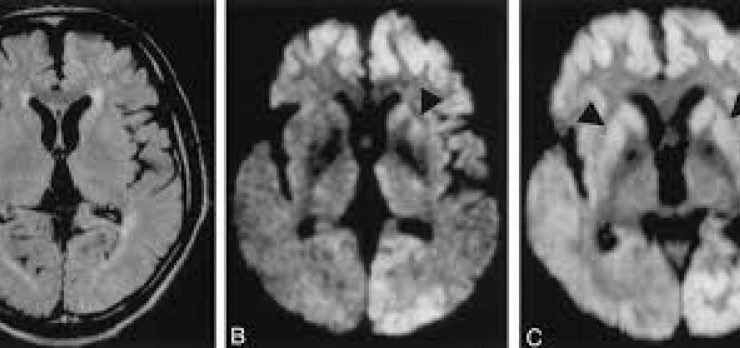

A Doença de Creutzfeld-Jakob provoca desordem cerebral, perda de memória e, de forma inevitável, leva à morte. A DCJ tem quatro tipos diferentes de manifestação.